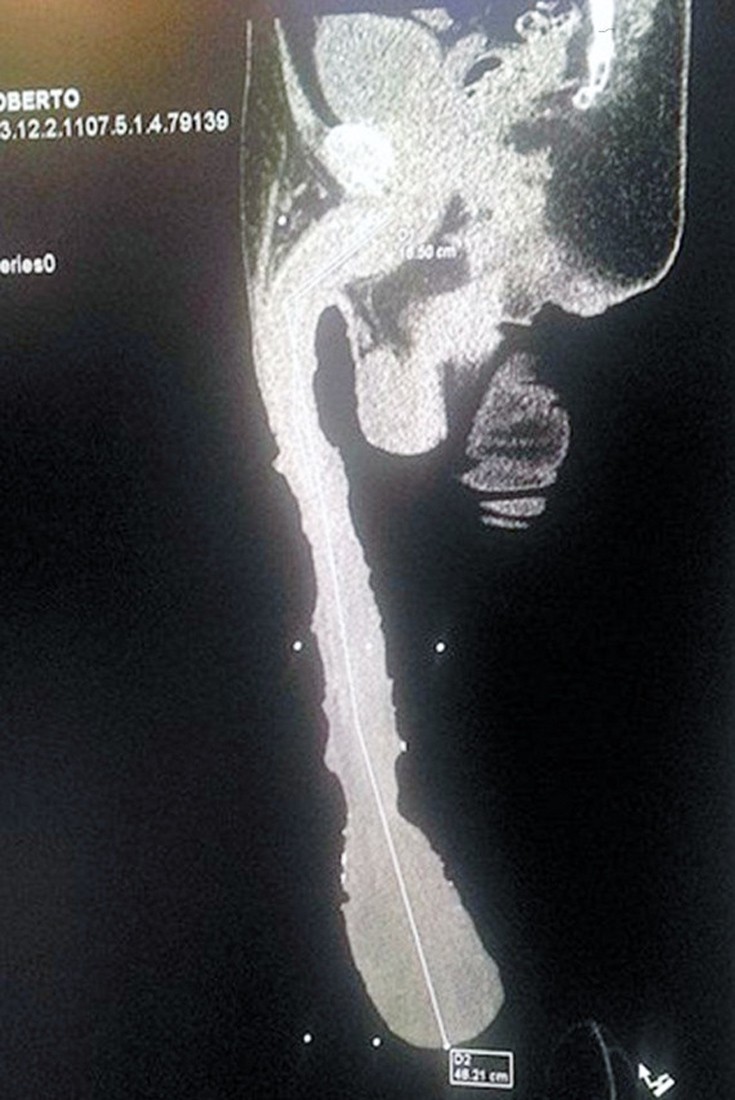

Μπορεί για άλλους να αποτελεί ευλογία και ευσεβής πόθος, αλλά όχι για τον Roberto Esquivel Cabrera. Ο 52χρονος Μεξικανός, ισχυρίζεται ότι διαθέτει το μεγαλύτερο μόριο του κόσμου, καθώς έχει μήκος 48 εκατοστά, αλλά αυτό δεν είναι κάτι που τον κάνει περήφανο. Όπως αναφέρει, το… ανδρικό του πλεονέκτημα, του προκαλεί μια σειρά από προβλήματα υγείας, εξαιτίας των οποίων δεν μπορεί να εργαστεί.

Ο Cabrera, απελάθηκε το 2011 από τις ΗΠΑ και πλέον ζει στο Saltillo, στο Μεξικό, με τα αδέλφια του, και στην ουσία συντηρείται από την πρόνοια. Πρόσφατα, υποβλήθηκε σε ιατρική εξέταση και έκανε μια ακτινογραφία προκειμένου να αποδείξει ότι το γενετικό του όργανο είναι αληθινό. Ο ίδιος θα ήθελε να δει το όνομά του στο βιβλίο των ρεκόρ Γκίνες, εντούτοις ο γιατρός που τον εξέτασε ανέφερε ότι το μόριό του έχει μόλις 15 εκατοστά μήκος και πως το υπόλοιπο είναι απλά δέρμα.

«Κοιτάξτε που είναι, φτάνει κάτω από το γόνατο», ανέφερε ο 52χρονος σύμφωνα με τα διεθνή μέσα. «Δε μπορώ να κάνω τίποτα, δε μπορώ να εργαστώ, είμαι ανάπηρος γι αυτό θέλω τις αρχές να με χαρακτηρίσουν ως ανάπηρο και να μου δώσουν κάποιο εισόδημα», σημειώνει. Για την ιστορία, μέχρι σήμερα το ρεκόρ διαθέτει ο Αμερικανός Johan Falcon, με μόριο μήκους 33 εκατοστών.